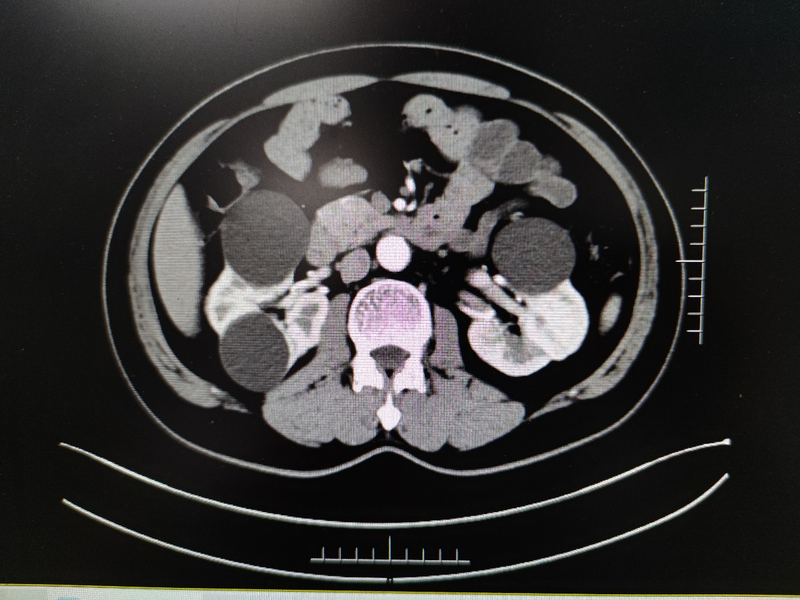

家住雨山的卞先生,現年53歲,因“檢查發(fā)現雙腎囊腫6年”在外院就診,CT檢查提示雙腎多發(fā)囊腫,左腎較大者4.8cm*4.7cm,右腎較大者為5.3c*5.2cm?;颊邥r有雙側腰部脹痛不適癥狀,外院醫(yī)生建議行后腹腔鏡下右腎囊腫去頂減壓手術治療,三月后再次行左腎囊腫手術?;颊弑救藶榘毯垠w質,加上對分期手術心存顧慮,想通過微創(chuàng)方式一次性同時解決雙側腎囊腫,但經過網上咨詢得到的絕大多數答復均需要行分期手術?;颊呶迥昵霸谖以盒小案文夷[去頂減壓手術”,秉承著對醫(yī)院的信任,再次來到醫(yī)院的泌尿外科就診。泌尿外科王龍信副主任接診后經仔細閱片,患者存在雙側腎臟多發(fā)囊腫,但囊腫大多位于腹側,存在行經腹單孔腹腔鏡手術同時處理雙側腎囊腫可能,遂收住入院。